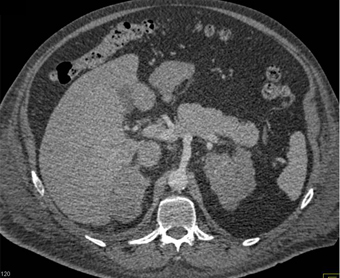

In this patient with no known malignancy the best diagnosis for the adrenal glands is?

occult adrenal metastases from unknown primary

adenomatous hyperplasia

adrenal hyperplasia

lymphoma